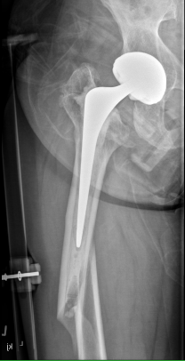

Long stem uncemented revision

Long stem uncemented revision with cortical strut allograft